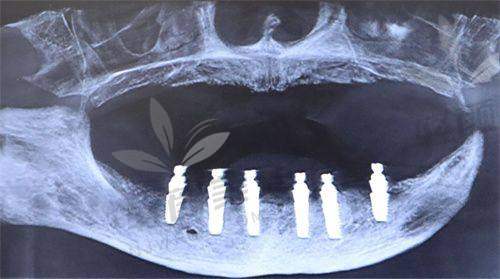

我提前在网上预约了时间,到了医院之后,前台的小姐姐特别热情,特别快就帮我安排了医生。给我看牙的是一位经验多的医生,他先给我做了全方面的口腔检查,包括拍X光片、取牙齿模型等等。然后根据我的检查结果,给我详细地分析了我的牙齿状况,还给我介绍了半口吸附性义齿和种植牙这两种修复方案。

医生说半口吸附性义齿比较适合我目前的情况,它是利用口腔黏膜和义齿基托之间的吸附力来固定义齿,佩戴比较舒适,而且价格相对种植牙来说要便宜一些。种植牙虽然成效更好,更接近自然牙,但是价格比较高,而且对牙槽骨的条件要求也比较高。我听了医生的介绍之后,觉得半口吸附性义齿更适合我,就决定选择这个方案。